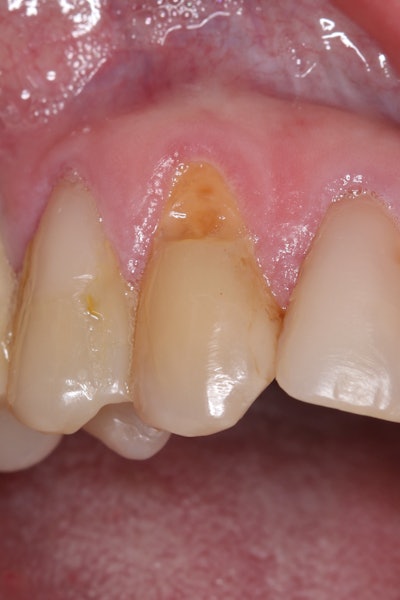

To improve isolation and soft-tissue access, a retraction cord was placed before initiating the procedure (Figure 2).

Figure 2: Placement of a retraction cord to improve isolation and access to the cervical area prior to preparation.Figure 2: Placement of a retraction cord to improve isolation and access to the cervical area prior to preparation.